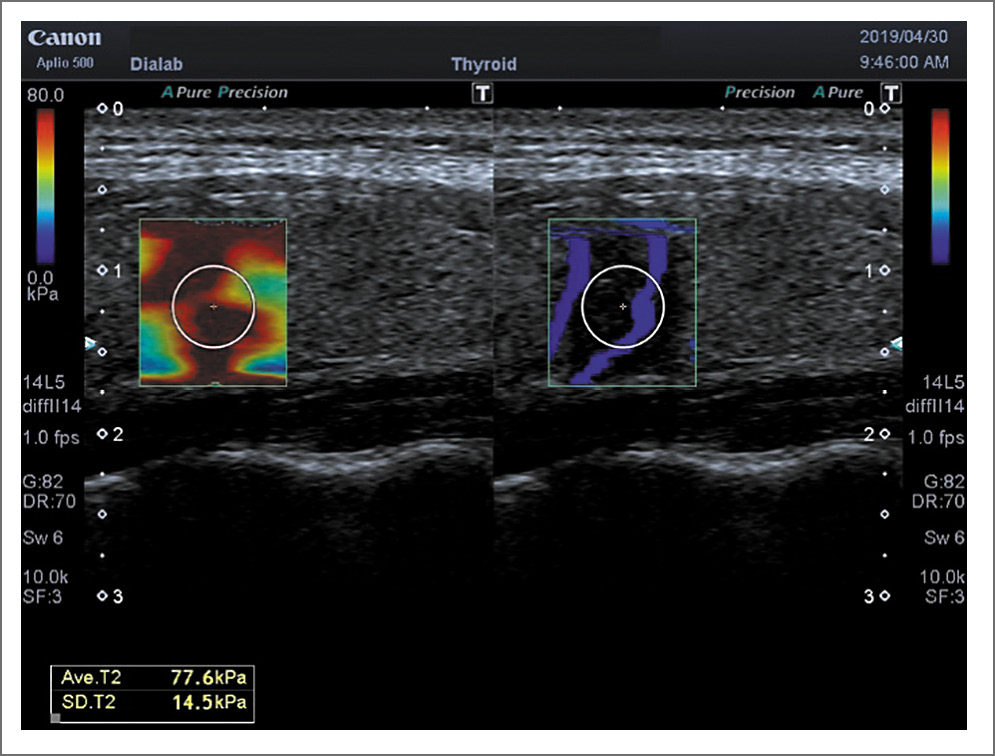

В литературе имеются единичные работы, посвященные этой проблеме. Так, F. Magri и соавт. (2012 г.) сравнили индекс эластичности нормальной ткани ЩЖ и при АИТ (24,0±10,5 кПа против 20,8±10,4 кПа; p=0,206). Авторы не получили также достоверных различий при соноэластографии доброкачественных УО при неизмененной паренхиме и на фоне АИТ [27]. По данным наших исследований модуль Юнга при АИТ составляет 32,05±2,14 кПа, что с высокой степенью достоверности (p<0,000) отличается от неизмененной паренхимы (15,9±0,87 кПа). При ПРЩЖ модуль Юнга достоверно выше (p<0,02), когда последний выявляется на фоне АИТ, чем без наличия фоновой патологии (72,03±1,09 и 67,0±1,9 соответственно); см. табл. 2, рис. 5, 6. Данные результатов наших исследований относительно доброкачественных УО (аденома, коллоидный зоб) показали те же закономерности и приведены в других публикациях.

Рис. 5. ПР. Shear Wave – 77,6 кПа